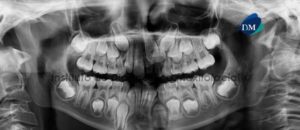

Paciente masculino, 12 años de edad es referido al Instituto de Diagnóstico Maxilofacial (IDM) para evaluación general.A la evaluación de la radiografía panorámica se aprecia